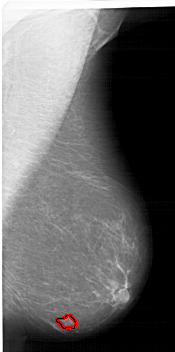

A_1422_1.LEFT_MLO

LEFT_MLO LINES 5956 PIXELS_PER_LINE 2506 BITS_PER_PIXEL 12 RESOLUTION 43.5 NON_OVERLAY

FILE: A_1422_1.RIGHT_MLO.OVERLAY

TOTAL_ABNORMALITIES 1

ABNORMALITY 1

LESION_TYPE MASS SHAPE IRREGULAR MARGINS ILL_DEFINED

ASSESSMENT 4

SUBTLETY 1

PATHOLOGY BENIGN

TOTAL_OUTLINES 1

BOUNDARY